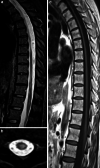

The recently developed effective treatment of primary progressive multiple sclerosis (PPMS) requires the accurate diagnosis of patients with this type of disease. Currently, the diagnosis of PPMS is based on the 2017 McDonald criteria, although the contribution of magnetic resonance imaging (MRI) to this process is fundamental. PPMS, one of the clinical types of MS, represents 10%-15% of all MS patients. Compared to relapsing-remitting MS (RRMS), PPMS differs in terms of pathology, clinical presentation and MRI features. Regarding conventional MRI, focal lesions on T2-weighted images and acute inflammatory lesions with contrast enhancement are less common in PPMS than in RRMS. On the other hand, MRI features of chronic inflammation, such as slowly evolving/expanding lesions (SELs) and leptomeningeal enhancement (LME), and brain and spinal cord atrophy are more common MRI characteristics in PPMS than RRMS. Nonconventional MRI also shows differences in subtle white and grey matter damage between PPMS and other clinical types of disease. In this review, we present separate diagnostic criteria, conventional and nonconventional MRI specificity for PPMS, which may support and simplify the diagnosis of this type of MS in daily clinical practice.